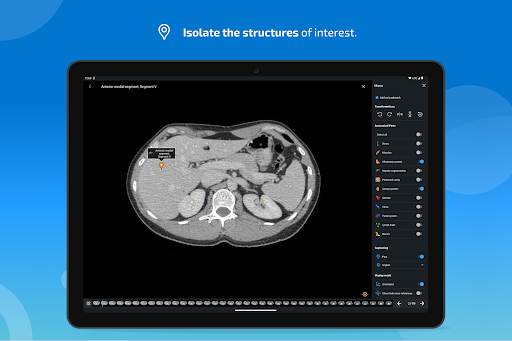

- يمكنك الآن إخفاء الهياكل واحداً تلو الآخر (زر جديد داخل نافذة الوصف المنبثقة) وعرضها مرة أخرى في القائمة الصحيحة